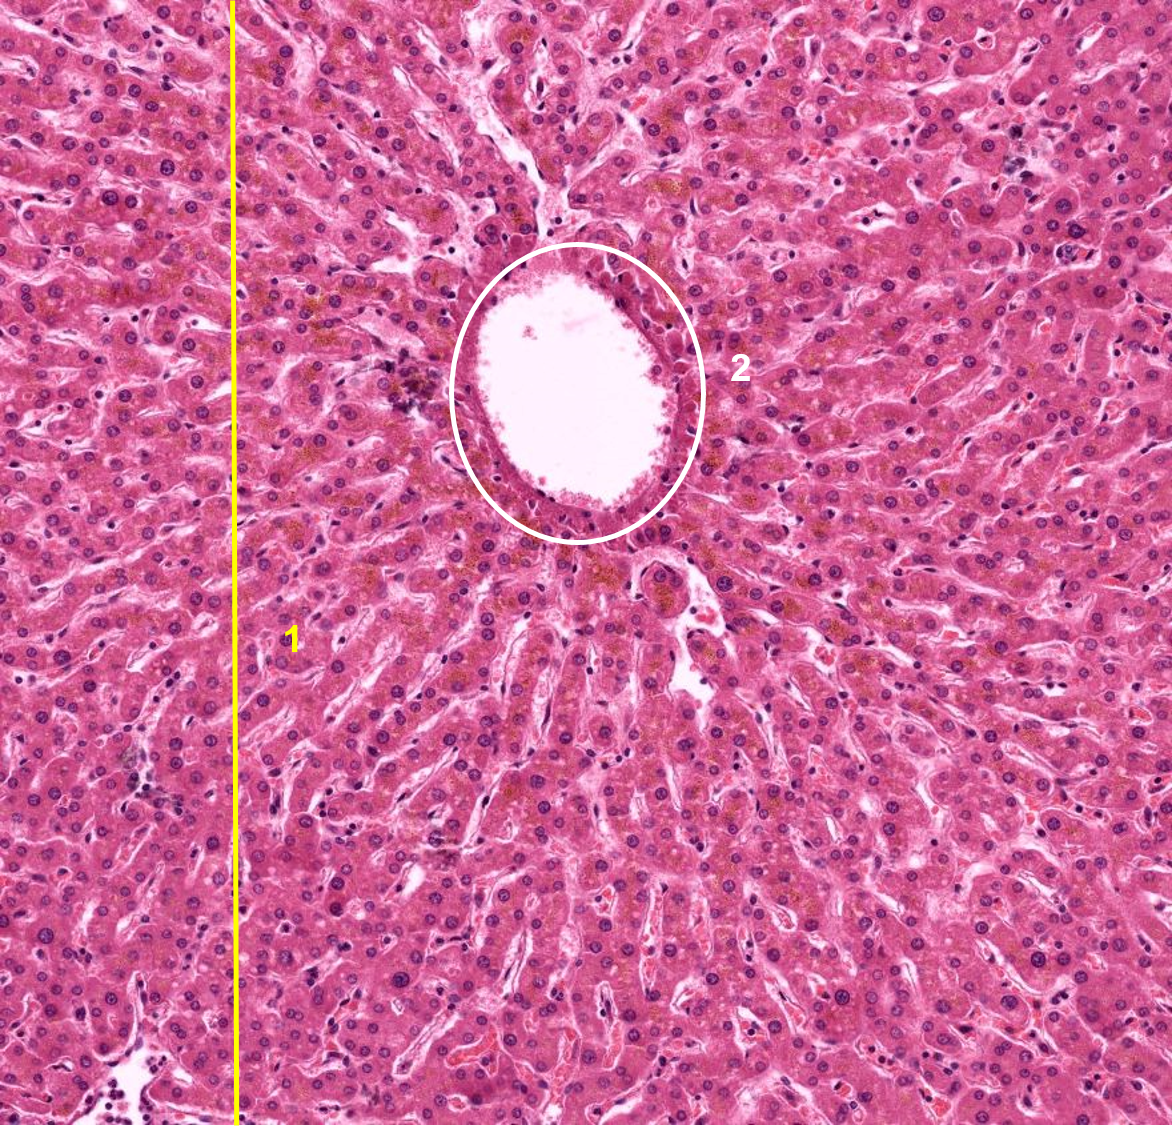

1: Fígado

2: Veia central